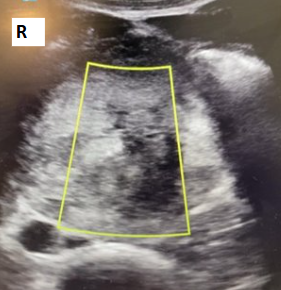

Historia clínica: Antecedentes personales: no enfermedades previas de interés, no antecedentes quirúrgicos, no alergias conocidas. Hábitos tóxicos: tabaco 1 paquete/día; cocaína, cannabis y TUSI, uso recreativo; alcohol, ocasional. Anamnesis: Paciente masculino de 28 años de aspecto atlético, que consulta por dolor abdominal de inicio súbito en epigastrio y mesogastrio, EVA 8/10, de 4-5 horas de evolución, sin otros síntomas asociados. Refiere consumo de anabolizantes (anabolizantes del GYM: boldenona, testosterona), además de proteína y creatina. Exploración: TA: 155/100 Abdomen: RHA presentes y conservados, abdomen blando, depresible, doloroso a la palpación superficial ni profunda en mesogastrio e hipogastrio. Sin signos de irritación peritoneal. Pruebas complementarias: Ecografía A pie de cama Se realiza barrido con sonda convexa; se observan dos masas lobuladas en la región del mesogastrio, heterogéneas e hiperecogénicas, derecha con área anecoica, diámetro aproximado de 16 cm, con paredes bien definidas, que no capta con Doppler. Tras control del dolor, se decide remisión al hospital de referencia, donde se completa estudio con analíticas, TAC y BAG de las lesiones: Analíticas: LDH 1,361 U/L (<300), PROTEÍNA C REACTIVA 17,19 mg/dL (<0,5), BETA-2 MICROGLOBULINA 2.903 µg/L (<2,5). BETA HCGMT 5,43 mU/mL (<5). TAC: CONCLUSIÓN: Las lesiones descritas presentan aspecto inespecífico, debiendo plantear dentro de diferentes posibilidades diagnósticas que correspondan a extensos conglomerados ganglionares o lesiones infiltrativas primarias/secundarias, incluso debiendo plantear como posibilidad tumores germinales. BAG de las lesiones eco guiada: Anatomía patológica SEMINOMA